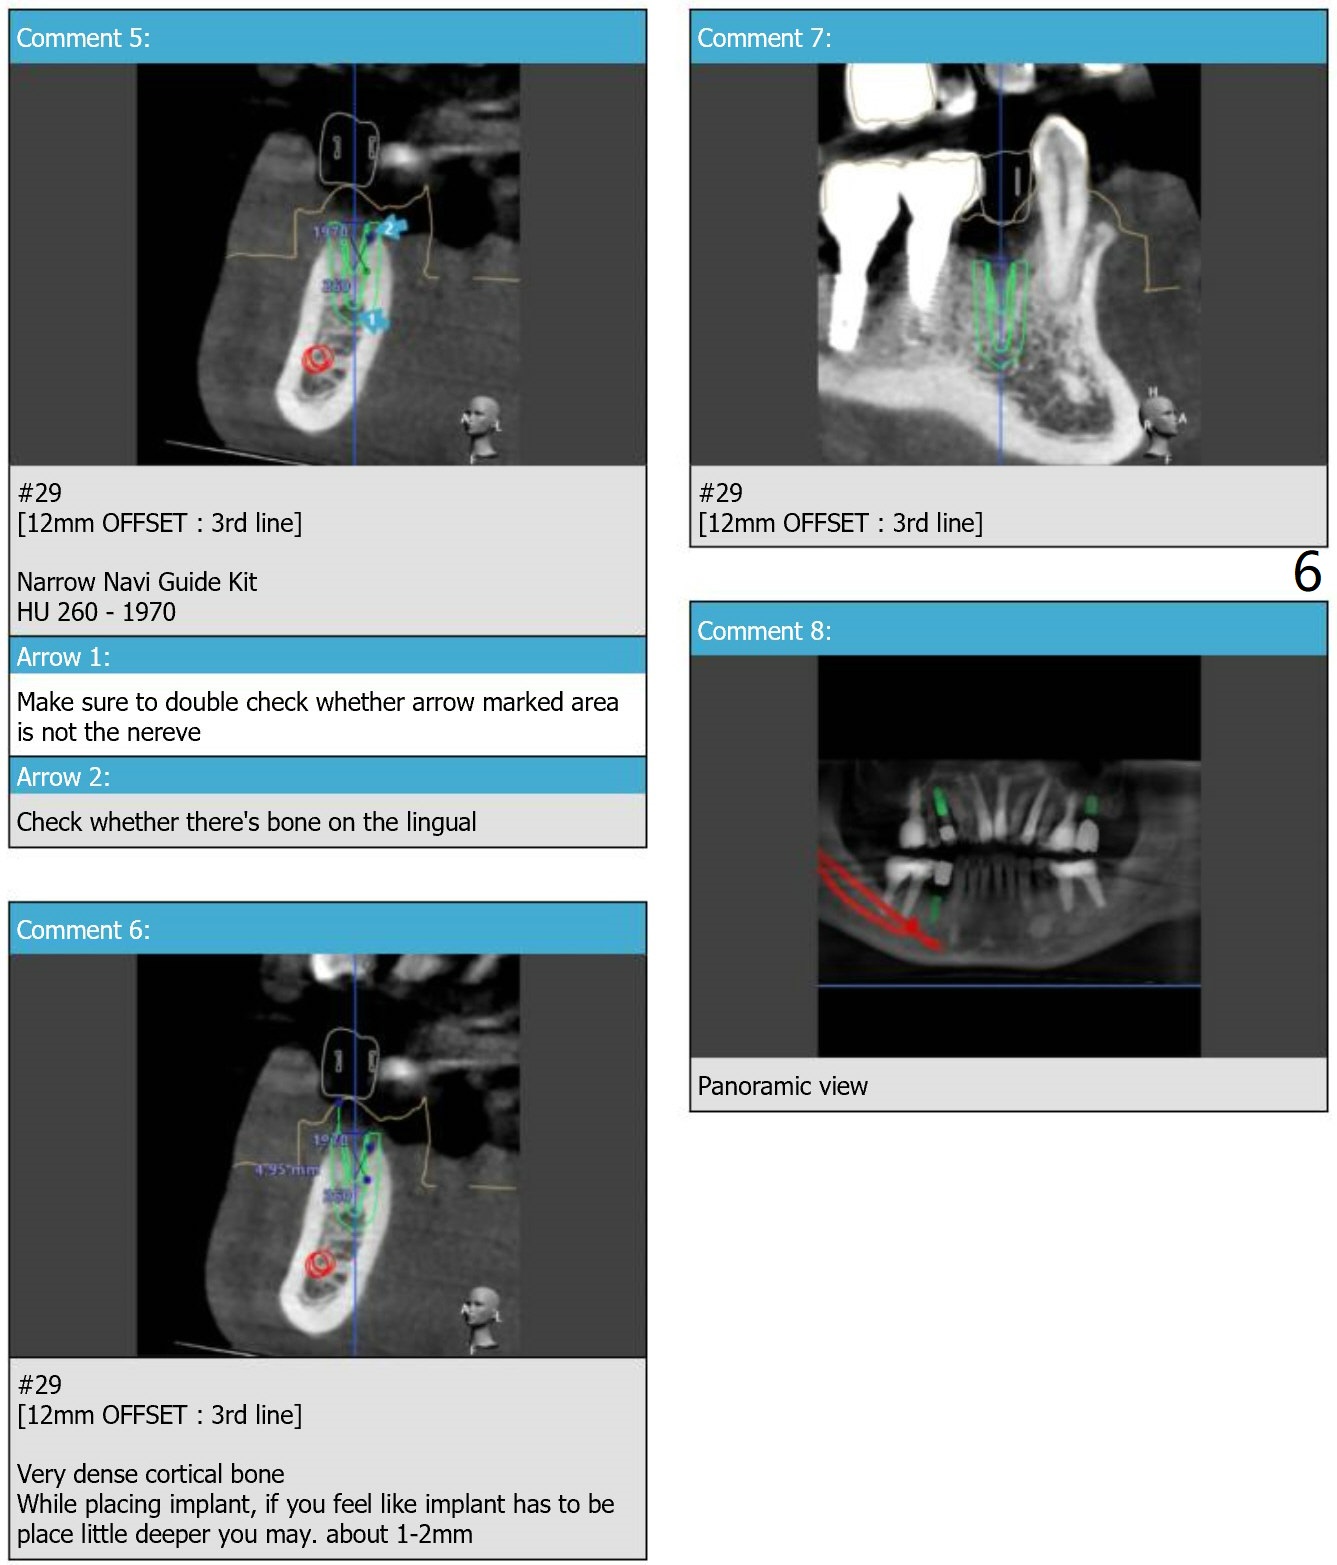

Cantilever

Restoration for Narrow Space

Because of the narrow space at #4 and 5, an implant will be placed slightly distal of #5 site and a cantilever FPD will be made at #4 and 5.